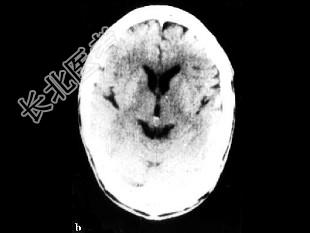

- 单项选择题女性患者56岁,突发黑朦2h, 无头疼及意识障碍,行99Tcm-ECD脑血流断层显像及CT扫描如图, 诊断为 ( )

C、左侧额叶、顶叶、颞叶TIA

D、左侧额叶、顶叶脑梗死

E、左侧大脑半球癫痫